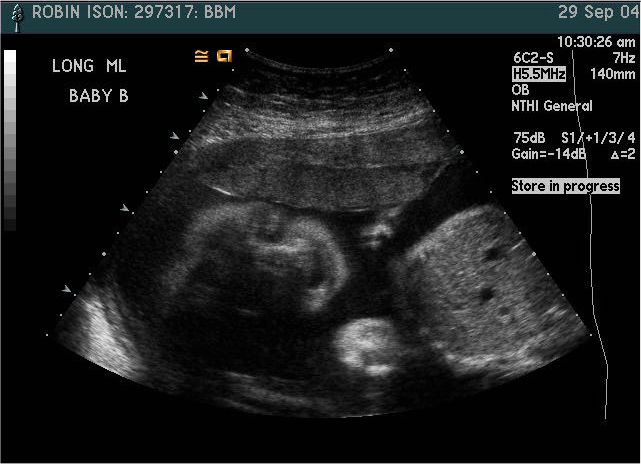

Baby B

Pictures from Ultrasound at 26 weeks.